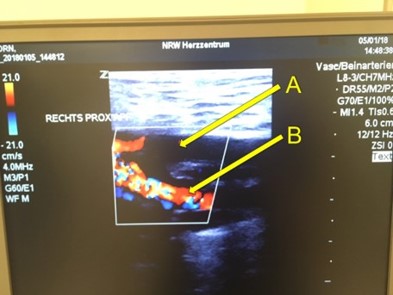

Figure 1: Ultrasound colour doppler image: A: no blood flow in right femoral superficial artery; B: preserved flow in profund artery

Ultrasound diagnostics showed no blood flow in the right femoral superficial artery. The vessel was punctured ultrasound-guided distal to the Impella, and a usual 4F sheath normally used for coronary diagnostics was introduced via seldinger technique after confirmation of the intravascular position of the guiding wire. The bypass of the sheath was connected to a second 5F sheath in the femoral artery of the contralateral leg using a special double-male adapter for connecting both sheaths.